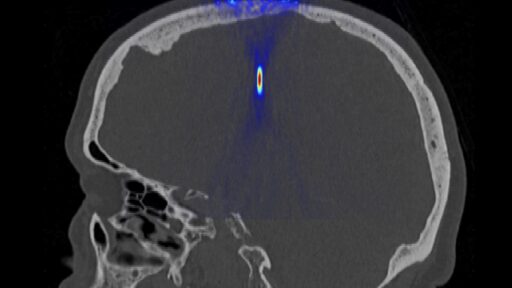

May 22, 2014 Ultrasound for non-invasive neurosurgery Development of non-invasive treatment modalities for brain tumors and neurodegenerative diseases Unrubricated

May 20, 2014 Ultrasonic methods in diagnostics and therapy of the brain Aberration correction, expansion of available brain area, ultrasound brain diagnostics Unrubricated